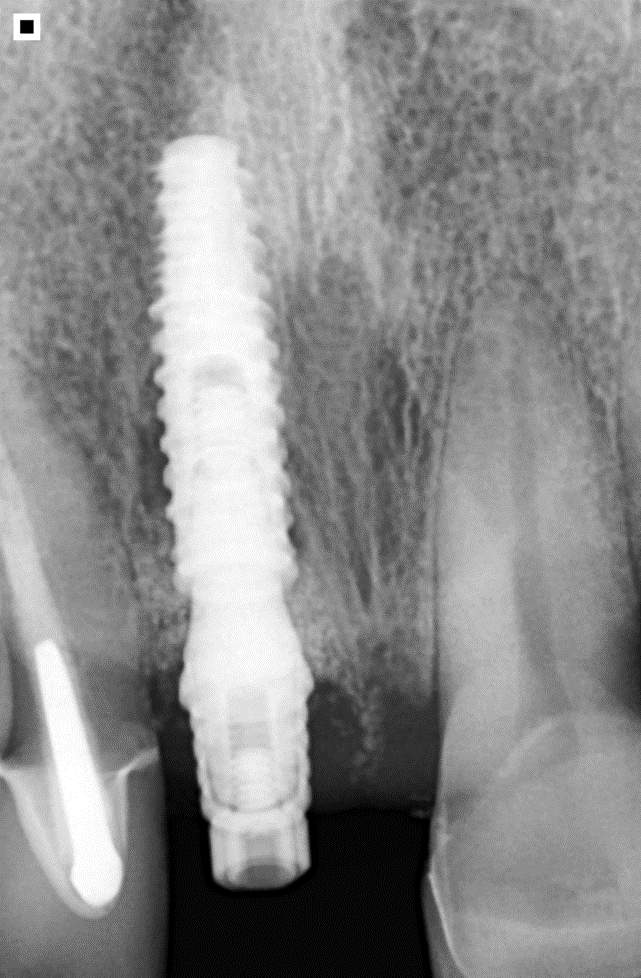

No presente caso, nossa paciente apresentou fratura (Figura 1) da raiz do elemento 11 (incisivo central superior direito), que já era reabilitado com pino intrarradicular (fibra de vidro + núcleo em resina) e coroa protética em cerâmica (dissilicato de lítio). Foi realizada exodontia minimamente traumática (Figuras 2 e 3), com manutenção das paredes ósseas e sem descolamento do tecido gengival ou abertura de retalho. Um implante Maestro (3.5 X 13 mm) foi instalado em posição tridimensional adequada e guiada pelo planejamento protético, no qual optamos por uma coroa parafusada (Figura 4). A profundidade de instalação foi conforme preconizada para um implante CM, e em seguida, um medidor de profundidade foi utilizado para selecionar o transmucoso do componente protético. Foi selecionado um pilar Ideale (3.3 X 4 mm) com transmucoso de 2.5 mm, favorecendo a adaptação dos tecidos moles e estabelecimento das distâncias biológicas peri-implantares (Figura 5).

Após dez dias da realização do procedimento cirúrgico, a paciente retornou para a consulta de pós-operatório, onde a sutura foi removida. Nesta consulta, foi possível constatar o sucesso do tratamento até aqui, pois foi observada saúde peri-implantar e estética extremamente favorável (Figura 10). A Figura 11 apresenta a radiografia final do implante. Contudo, o dente foi deixado fora de função para proteção do implante no período de osseointegração (45-60 dias, no caso do implante Maestro), por isso, só poderemos afirmar que alcançamos sucesso após esse período, onde a coroa definitiva será colocada em função mastigatória. Seguiremos buscando alcançar a tríade saúde, função e estética.